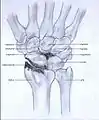

Post-traumatic osteoarthritis can be classified into four stages.[1][6] These stages are similar between SLAC and SNAC wrists. Each stage has a different treatment.

- Stage I: the osteoarthritis is only localized in the distal scaphoid and radial styloid.

Stage I